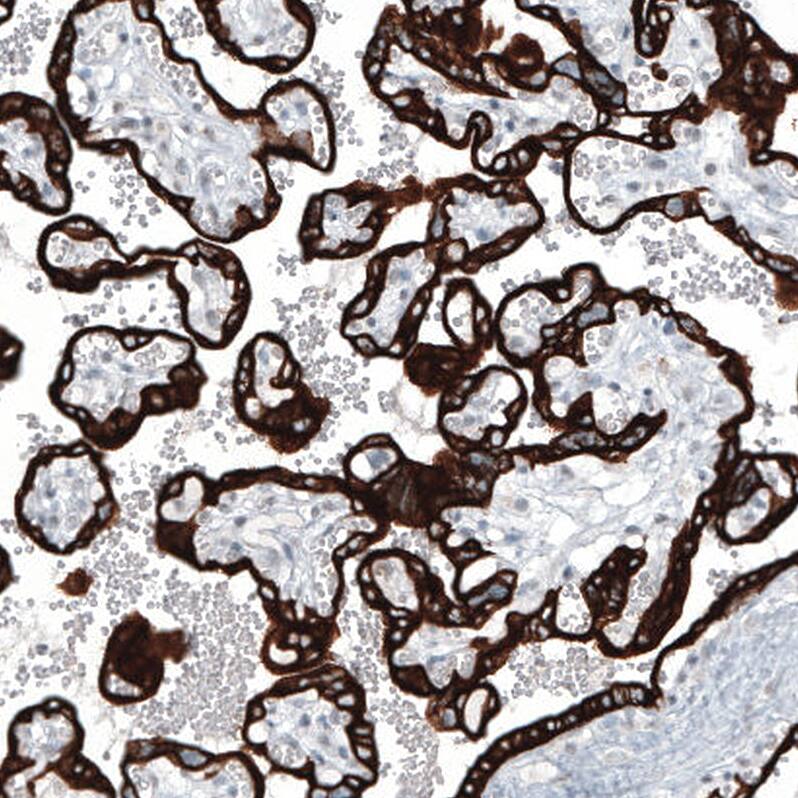

Staining of human placenta shows strong cytoplasmic positivity in trophoblastic cells.